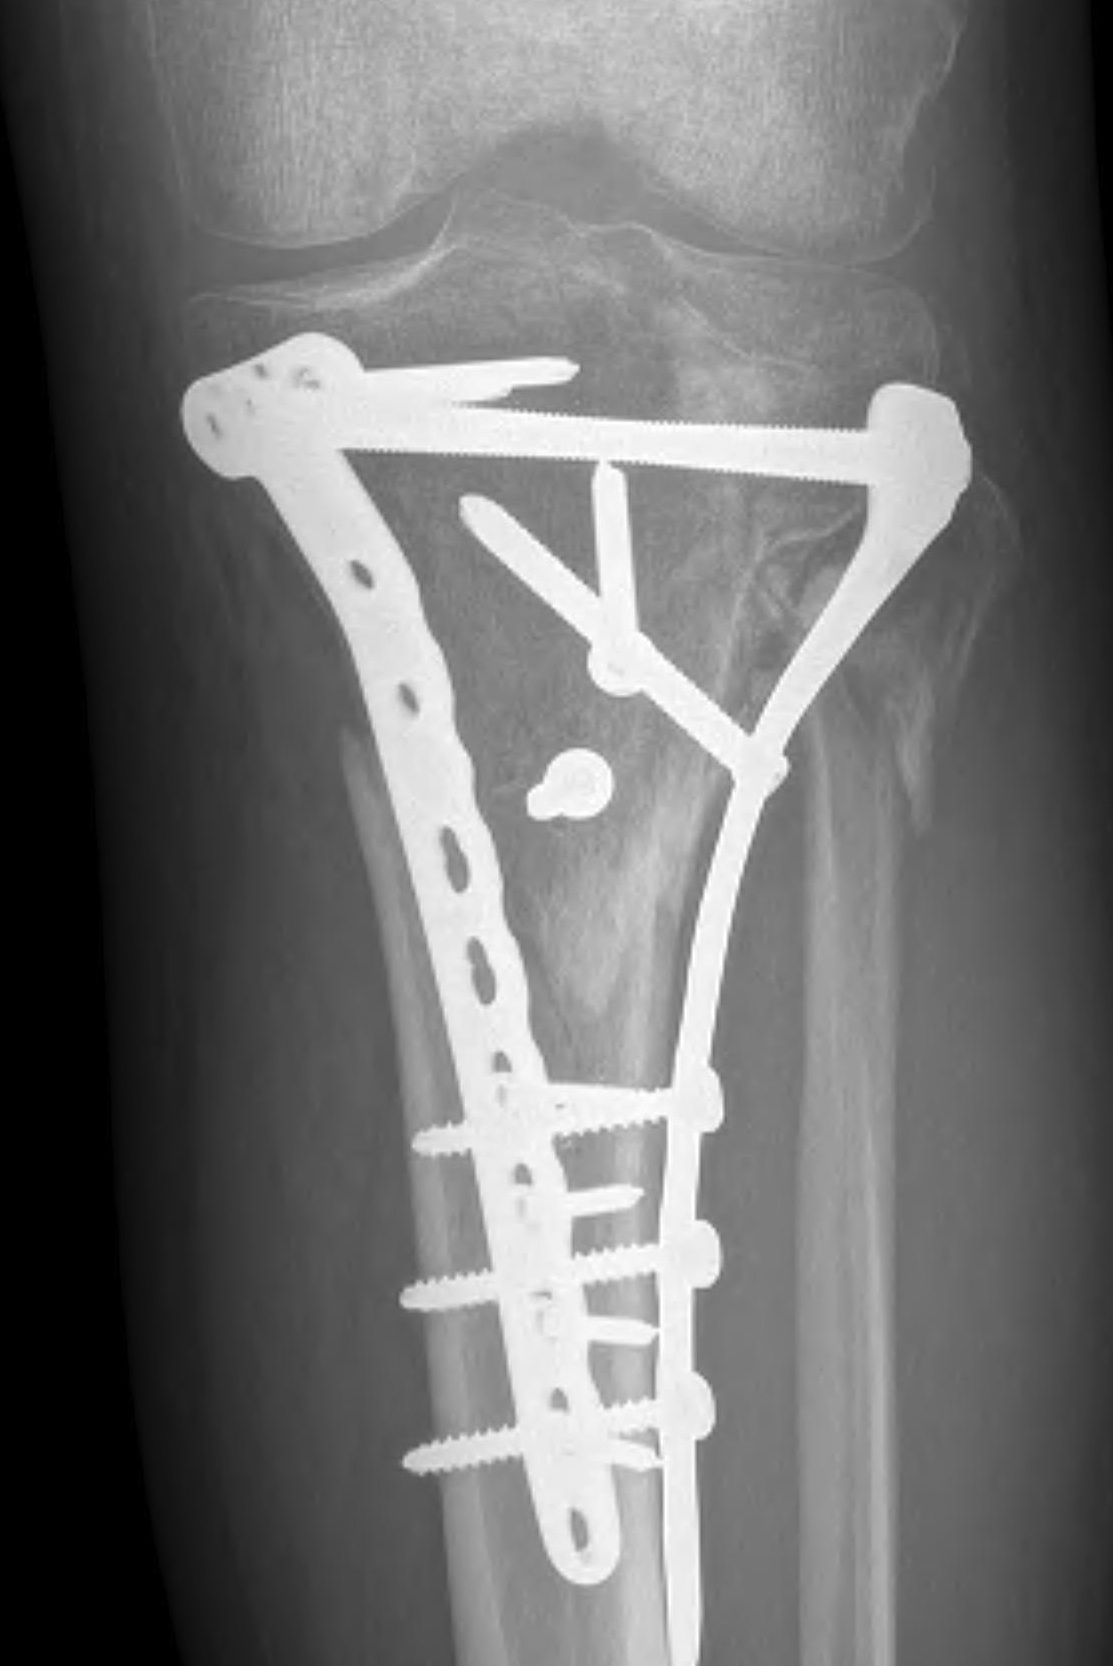

Type V Bicondylar

Options

1. Medial and Lateral plating

Technique

- depends on which of the three columns affected

- anterolateral approach for lateral column

- posteromedial appraoch for medial / posterior column